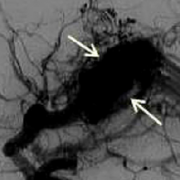

脑动静脉畸形 (AVMs)是血管系统的缺陷,由异常血管缠结(nidus)组成,其中供血动脉在没有毛细血管床的介入下,直接连接到静脉引流网络。动脉将富含氧气...

人脑动静脉畸形 (脑动静脉畸形)是大脑循环系统的缺陷,通常认为是在胚胎或胎儿发育过程中出现的。通常,含氧血液由心脏通过分支动脉(称为动脉)...

目前比较普遍的观念认为颅内动静脉畸形是一种先天性的疾病,是多种原因导致的胚胎时期血管发育异常所致。本病的年发病率约为1.12~1.42/10万人,其中...